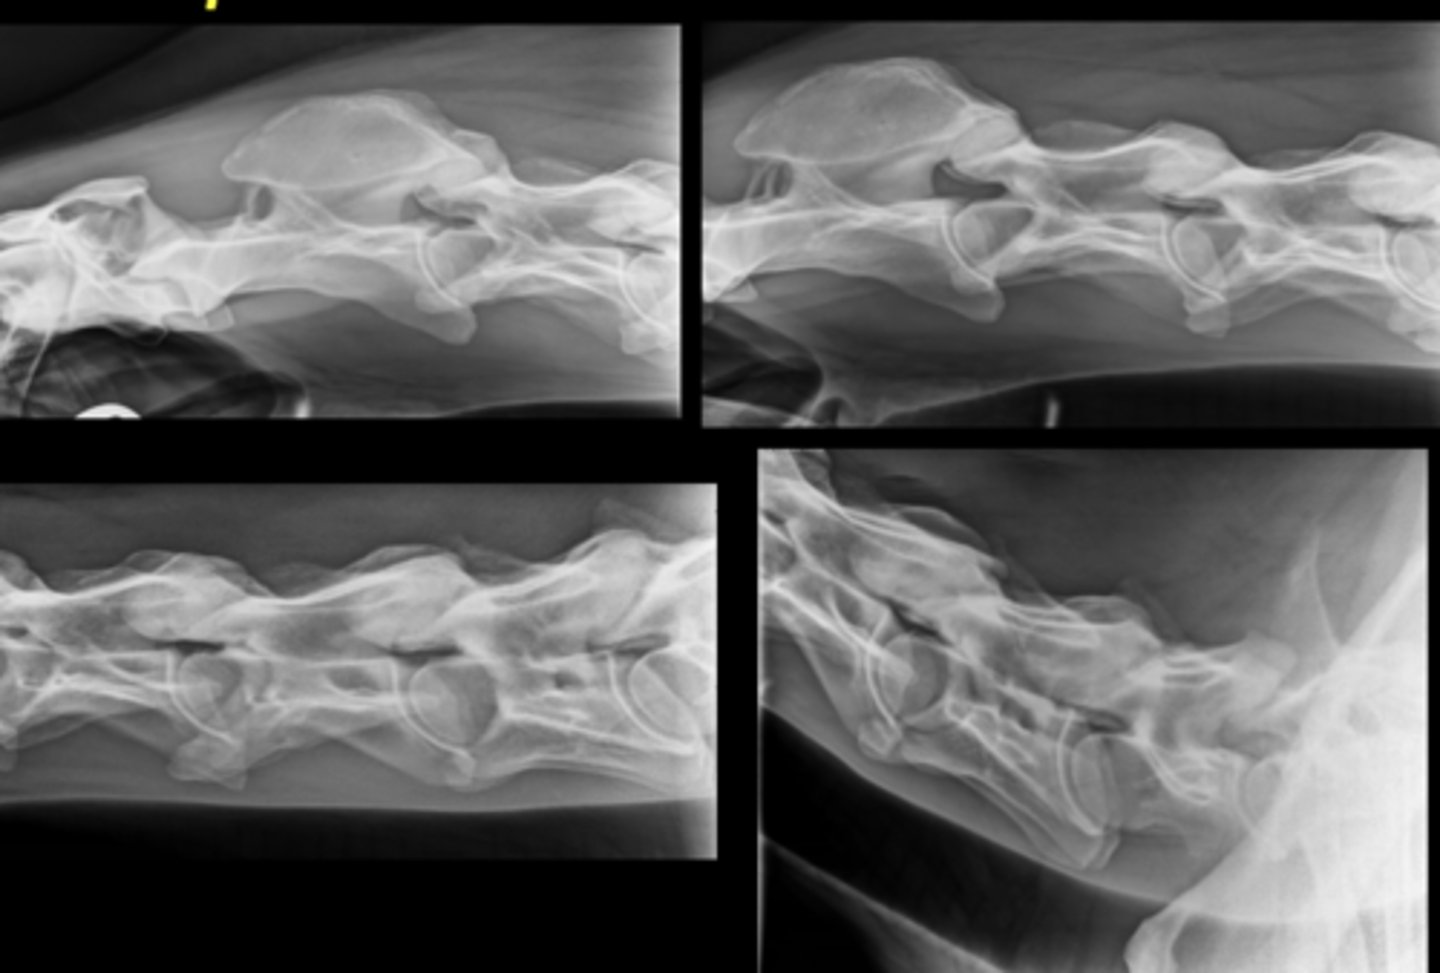

Equine Spine Lateral

Llama Spine Lateral

Bovine Spine Lateral